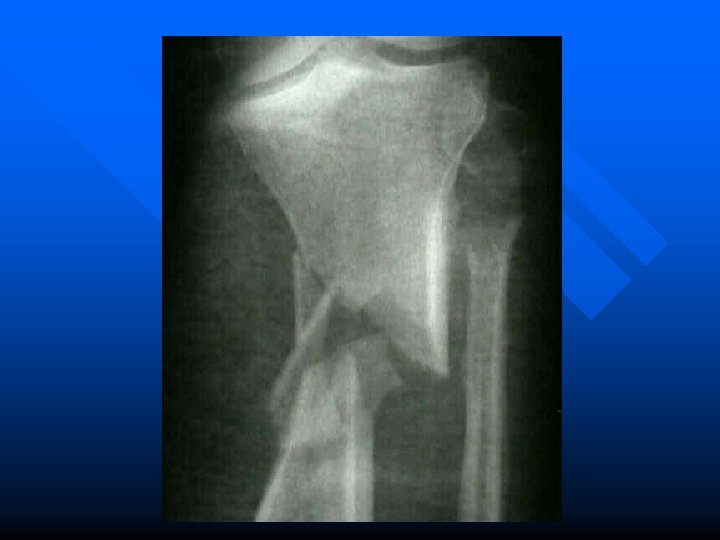

n Eversion - usually due to a planted foot that receives a lateral force

n Eversion - usually due to a planted foot that receives a lateral force - stepping in a hole - higher incidence of fractures

Medial Ligament Sprain (Deltoid Ligament) n Often associated with fractures of lateral malleolus